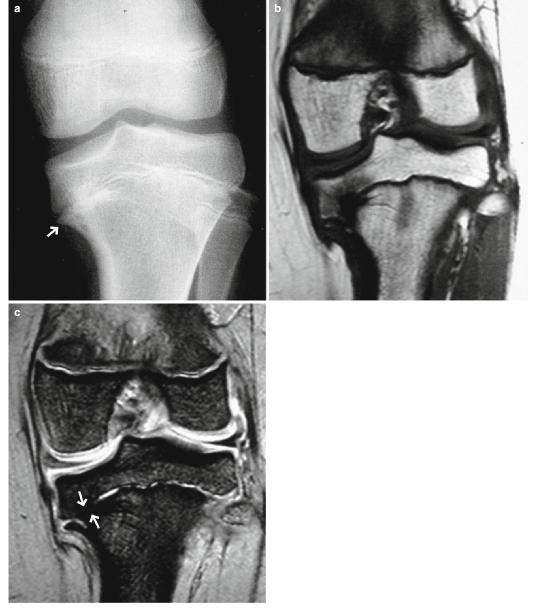

- MRI可直接显示骺板(图9.19)。

图9.19布朗特病。一个9岁的女孩。(a)前后位x线照片,(b)冠状位T1WI,以及(c ) T2*WI。胫骨内侧骨骺和干骺端在x线片上显示不规则和喙状畸形(箭头)。MRI显示骺板早期闭合,如图所示骺软骨信号丢失(箭头,c)